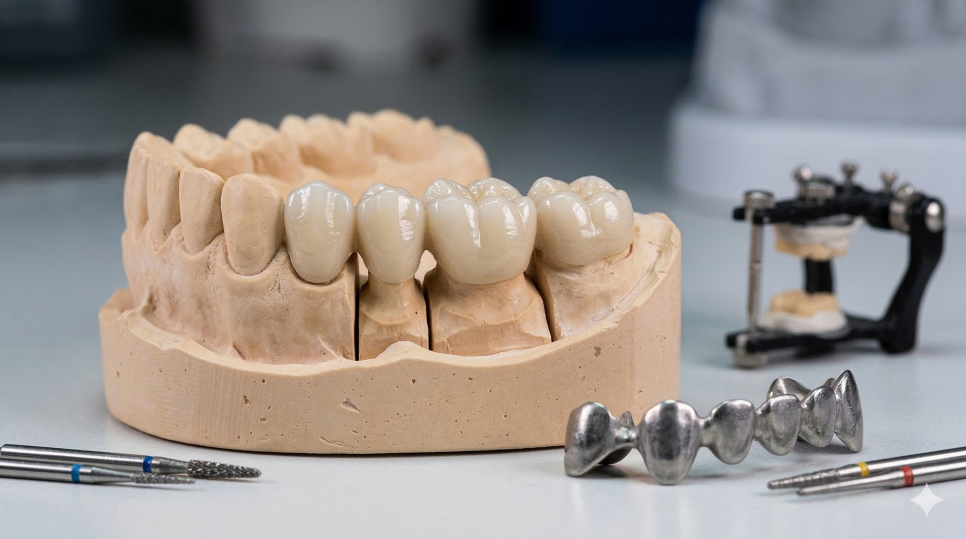

저희는 과거에 많이 사용하던

끈적이는 고무 재료로 본을 뜨지 않고

구강 스캐너를 이용하여 컴퓨터로 빠르게 싹~

본을 뜨기 때문에 환자분들이 매우 편안해하세요!

디지털로 스캔한 자료는 원내 기공소로 넘어가

이 데이터를 가지고 최적의 보철물을

제작합니다.

240319

꼼꼼하고 정교한 디지털 과정을 거친 덕분에

만족스러운 보철물이 완성되었네요.^^